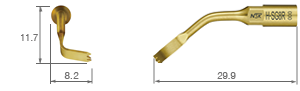

Unilateral anterior mandibular sampling

Excision of bone torus

Anterior mandibylar harvesting

Mandibular harvesting at approach stage

The cutting part is bone torus

• POWER LEVEL [SURG] 80%

• TiN coating

• 11 teeth ; 0.6 mm thick